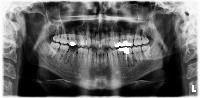

Dental Diagnosis Aid: A computer vision application that assists dentists in diagnosing and identifying various dental issues, such as cavities, impacted teeth, and periodontal bone loss, helping them create a comprehensive treatment plan for their patients.

Dental Education: A tool for dental students and professionals to practice identifying restoration classes on anonymized patient X-rays, enabling them to become more proficient in diagnosing oral health problems.

Dental Insurance Analysis: An application for dental insurance companies to assess the complexity and coverage requirements of dental treatments based on the identified restoration classes, streamlining claim processing and reducing the potential for fraud.

AI-Powered Dental Imaging Software: A feature in dental imaging software that automatically annotates and highlights areas of interest related to various restoration classes, saving time for dental practitioners and improving patient communication.

Dental Research and Data Analysis: A tool for oral health researchers to quickly identify and categorize various dental restoration classes within large datasets, allowing them to conduct more efficient studies and generate valuable insights into oral health and treatment patterns.